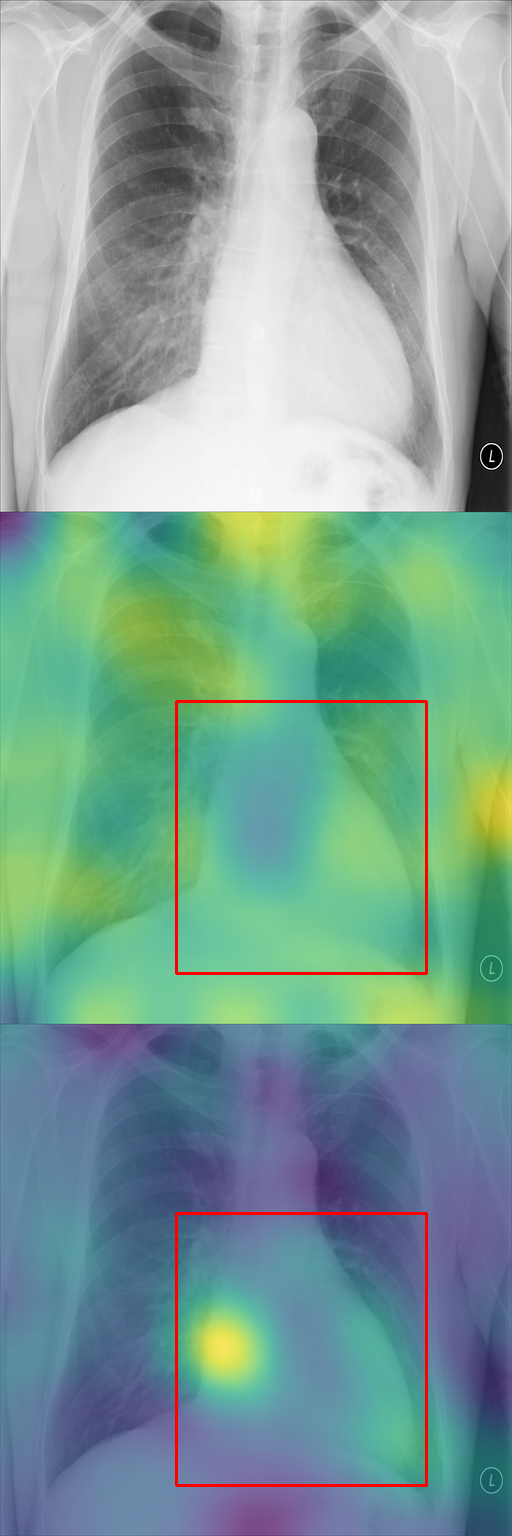

In Section 4.2, we discussed how typicality helps find relevant patches for an input label. In this section, we test this idea on completely different images: X-rays of patients who may suffer from a combination of various thorax diseases. We finetune Stable Diffusion on the ChestX-ray8 dataset [46] containing 108,948 frontal-view X-ray images annotated with 14 single-word disease-name labels. Experts annotated a test set of 879 images with 7 diseases with rectangular regions of interest (ROI) for each disease. For each image, we compute typicality per latent feature, interpolate the resulting typicality to the input dimension, and blur the resulting typicality map for visualization. In Fig. 11, we show the resulting typicality maps together with the ROI annotation before and after finetuning. Finetuning clearly improves the localization. We quantify this effect by computing the area under the precision recall-curve [5] (AUC-PR) associated with the ROIs. As reported in Fig. 11, we see consistent improvement of this measure when finetuning the network (from 3.2% to 9.6%), ranging from +3.5% for Pneumonothorax (from 3% to 6%) to +14.6% for Mass (from 2% to 16.6%), which are respectively the least and most localized diseases. Similar to our other experiments, finetuning uses only image labels without localization supervision.